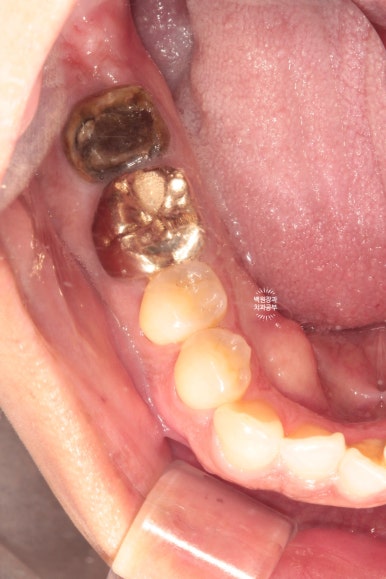

머리가 부러진 오른쪽 아래 어금니...

충치라고 생각되는 부위를 조심조심 제거해보았습니다.

보시면 안에 분홍색으로 동그랗게 보이시는게 있죠?? 옛날에 신경치료 때 사용했던 재료에요!

GP cone 입니다.

그 정도로 제거했는데도 여전히 까만색의 치아만 남아있네요...

이 치아는 뿌리 내부까지 썩었다고 판단되어 뽑기로 결정하였습니다.